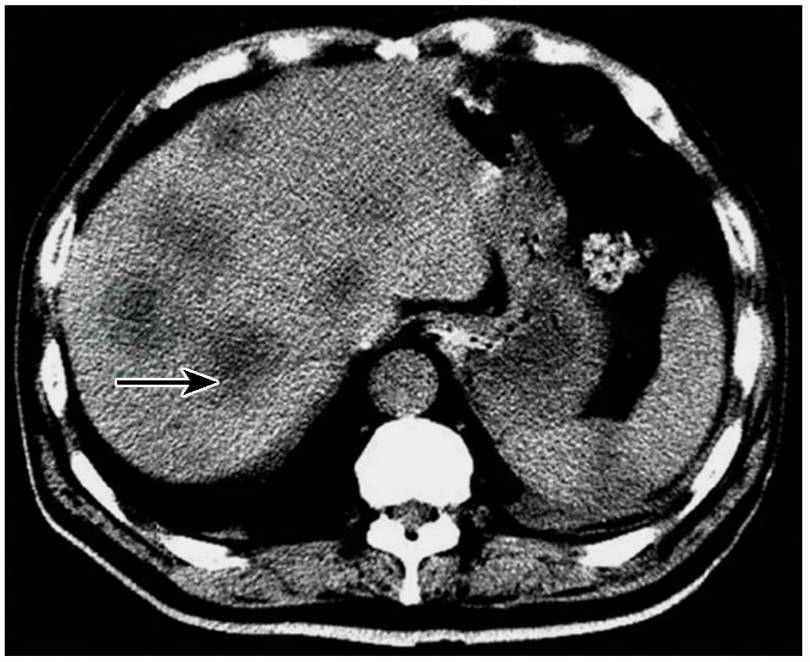

9.腹部CT平扫

脂肪肝;肝脏多发低密度占位,考虑为转移瘤;右肾囊肿(因患者嗜睡状,CT室医生未行增强扫描)(图3)。

图3腹部CT平扫见肝脏多发低密度占位影(箭头)